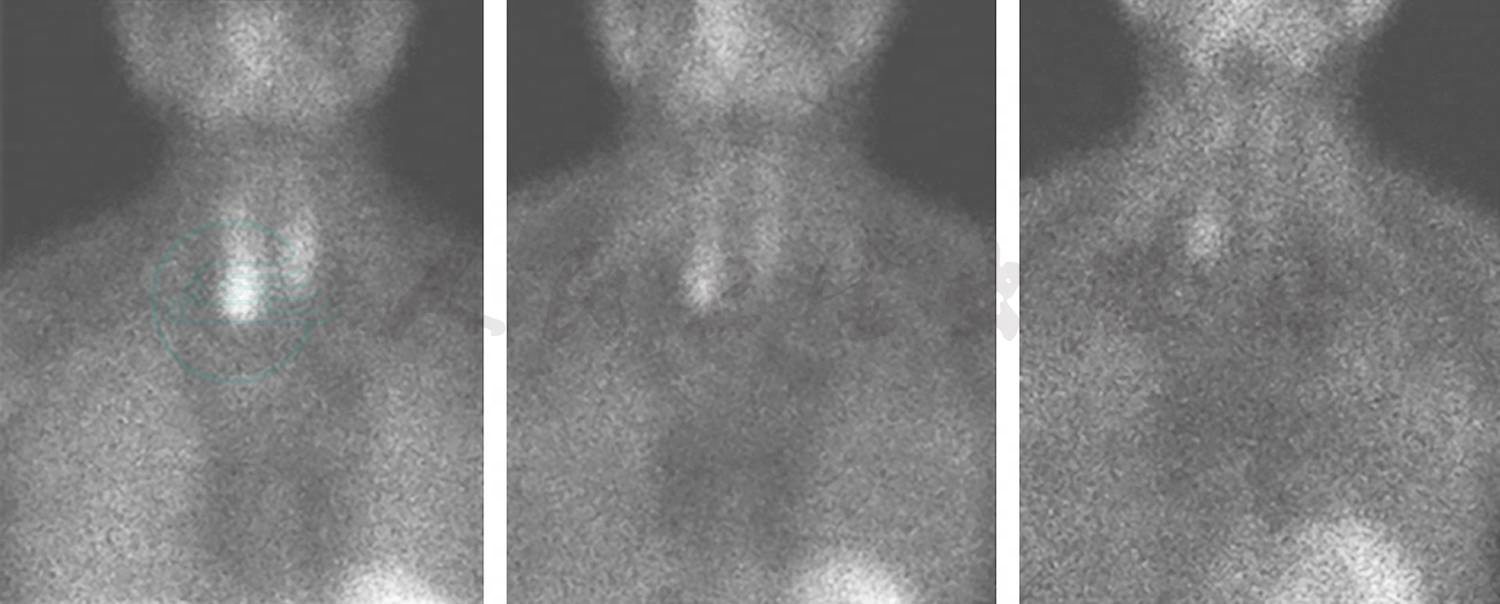

99mTc-MDP骨闪烁显像:双肺野可见类似骨显像影(图7)。

图7 99mTc-MDP骨闪烁显像

引自:主编:.呼吸系统疑难病例诊疗辨析.第1版.ISBN:978-7-117-26415-0

术后11个月,胸部CT示双肺多发斑片影明显减少,左下肺钙化及心室壁钙化较前减轻(图9);99mTc-MDP骨闪烁显像示双肺野骨外显影较前好转(图10)。

图10 术后11个月99mTc-MDP骨闪烁显像

MPC的诊断较困难,特别对于钙-磷乘积正常者,若排除了其他可能引起肺钙化的疾病,如结核、肺泡微结石症、矽肺,需要考虑MPC的可能。99mTc-MDP骨闪烁显像术有助于协助诊断。钙-磷乘积是指血钙、血磷值[以百分毫克(mg/dl)为单位)的乘积,正常值为30~40。其中,[Ca]1mmol/L= 4mg/dl;[P]1mmol/L=3.1mg/dl。若([Ca]×[P])>40,则钙和磷以骨盐形式沉积于骨组织;若([Ca]×[P])<35,则妨碍骨的钙化,甚至可使骨盐溶解,影响成骨。

根据辅助检查结果,考虑本病例病因为原发性甲状旁腺功能亢进,手术切除甲状旁腺,病理检查显示为甲状旁腺腺瘤。甲状旁腺激素分泌过多可致高钙、低磷。本例患者钙磷乘积在正常范围内,经支气管肺活检见肺泡腔及肺泡隔有多量钙化物沉积,胸部CT见两肺散在斑片状影,99mTc-MDP骨闪烁显像见双侧肺野骨外显影,排除了肺结核、矽肺等常见疾病。因此,本病例诊断为甲状旁腺腺瘤伴发转移性肺钙化。

MPC的治疗以控制钙磷平衡为主,积极治疗引起钙磷代谢紊乱的病因,如慢性肾功能不全、原发或继发性甲状旁腺功能亢进等,病情可好转。本病例影响钙磷平衡的主要原因为甲状旁腺腺瘤,手术切除病变的甲状旁腺,术后11个月复查胸部CT显示病灶较前明显吸收。

以呼吸系统症状和体征为首发表现的原发性甲状旁腺功能亢进较少见,容易误诊为肺部疾病。提高对原发性甲状旁腺功能亢进的认识是明确诊断的前提。如果患者出现呼吸道症状,且影像学表现可见多发钙化影,应甄别转移性肺钙化可能,及时获取肺部病变组织病理检查结果,完善99mTc-MDP骨闪烁显像检查,以协助诊断。